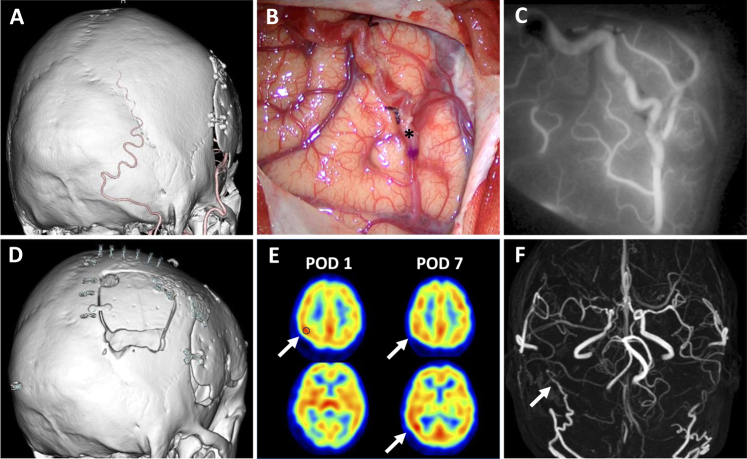

Observations: The authors report the case of a 50-year-old woman with MMD who developed symptomatic hemodynamic compromise due to progressive right PCA stenosis 10 years after bilateral superficial temporal artery-middle cerebral artery bypass and indirect revascularization. She underwent OA-PCA bypass with encephalo-myo-synangiosis. On postoperative day 1, single-photon emission CT revealed focal CHP in the right parietal lobe, with cerebral blood flow (CBF) increasing to 160% of preoperative levels. The patient developed a pulsatile headache and left-sided tongue numbness. By postoperative day 7, CBF had decreased to 110%, and perfusion had improved throughout the right parietal-occipital region. With strict blood pressure control and minocycline administration, both symptoms and CHP resolved. At the 1-year follow-up, the patient remained symptom free without stroke recurrence.